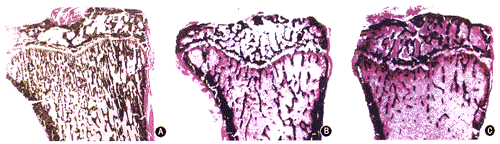

1.骨组织形态计量学指标的变化:(1)胫骨近端次级骨小梁静态指标的变化:OVX后骨小梁面积比率(Cn-BV/TV)显著减少,经阿法骨化醇治疗后,O+VD比OVXe增加106.7%(P<0.01),但仍显著低于Sham(P<0.01)。O+E的Cn-BV/TV比OVXe增加122.3%,而与O+VD之间差异无显著意义(P>0.05)。同时O+VD和O+E的松质骨的结构改善明显(表1,图1)。

图1 大鼠右侧近端胫骨切片,可见A.(Base)和B.9

月龄(Sham)组次级骨小梁致密,结构完整;C.7

月龄(OVXb)和D.9

月龄(OVXe)组的骨小梁稀疏,尤其是OVXe更明显;E.9

月龄(O+E)和F.9

月龄(O+VD)组的骨小梁数目比OVX组有显著增加,结构改善 Von Kossa染色 ×10